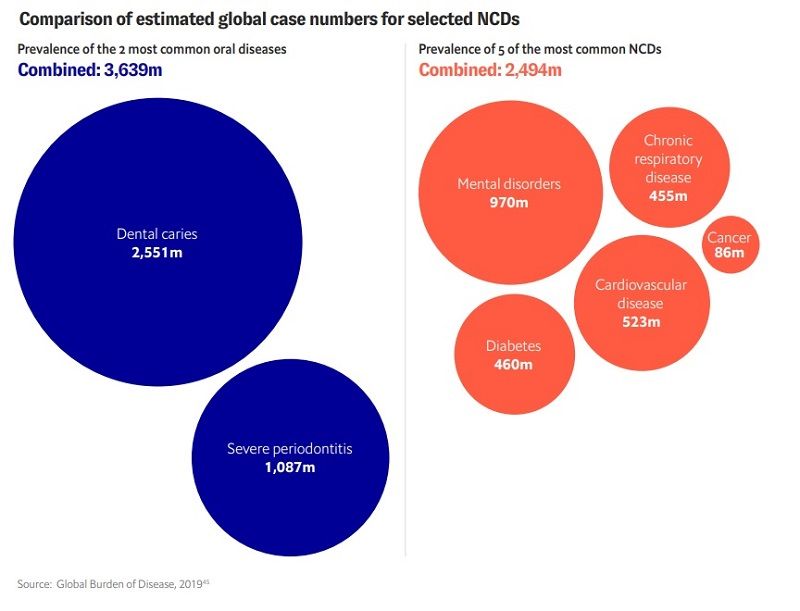

Bajo el título “Es hora de poner su dinero donde está su boca: abordar las desigualdades en la salud bucal”, el informe revela que las enfermedades bucales, como las caries no tratadas y la periodontitis severa, representan una carga significativa para la salud pública a nivel mundial. Según los datos del Estudio Global de Carga de Enfermedad de 2019, las caries no tratadas se han convertido en la afección de salud más común entre adultos y niños menores de 14 años, con un aumento del 46% en el número total de personas afectadas entre 1990 y 2019. Asimismo, se observó un aumento del 99% en los casos prevalentes de periodontitis severa en el mismo período.

Dado que casi la mitad de la población mundial está afectada por enfermedades bucodentales, superando a las enfermedades no transmisibles (ENT) más comunes, el libro blanco exige medidas urgentes. La caries dental afecta a más de dos mil millones de personas en todo el mundo. Le siguen las enfermedades graves de las encías, con más de mil millones de casos.